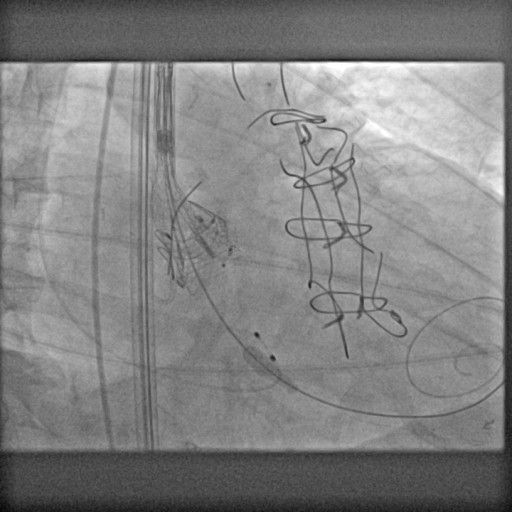

After creating an artero-venous loop between a transeptal and an arterial system, two vascular plugs (AVP III 10×5 and AVP III 8×4 ) were positioned and released, with their final position checked at TEE.